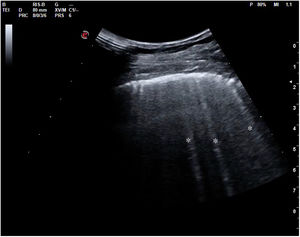

En el pulmón, la ecografía se comporta como un densitómetro. En un pulmón aireado (ya sea normal o con hiperaireación, como ocurre en el enfisema), la gran diferencia de impedancia acústica entre la pared torácica y el aire no permite obtener una imagen anatómica. En este caso, se evidencia la línea pleural, una franja horizontal hiperecogénica altamente reflectante del haz de ultrasonido. En el corte longitudinal (fig. 13), la línea pleural aparece entre 2 costillas sucesivas, en el denominado signo del murciélago: las corticales de las costillas, hiperecogénicas y con sombra posterior, constituirían las alas del murciélago, y la línea pleural, el cuerpo. En el corte oblicuo o intercostal (fig. 14), la línea pleural se presenta en su máxima extensión. Es una estructura dinámica, que se desliza con los movimientos respiratorios en el denominado deslizamiento (o «sliding») pleural. Al tratarse de una superficie altamente reflectante del ultrasonido, genera unos artefactos en profundidad, denominados líneas A. Las líneas A son hiperecogénicas, horizontales y paralelas, siempre a la misma distancia entre ellas (que es la misma distancia que hay entre la línea pleural y la sonda). Su presencia indica que la sonda está colocada perpendicular a la pleura, y no traduce enfermedad.

Cuando hay una pérdida parcial de aireación por ocupación del espacio intersticial (ya sea por líquido o por tejido fibroso), aparecen en la ecografía las denominadas líneas B (figs. 15 y 16). Las líneas B son artefactos verticales, también denominados en cola de cometa o láser-like, hiperecogénicos, que nacen de la línea pleural y alcanzan el final de la pantalla sin atenuarse. Se mueven sincrónicamente con el deslizamiento pleural. Pueden hallarse de forma aislada (en el síndrome intersticial focal), o difusa y bilateral.